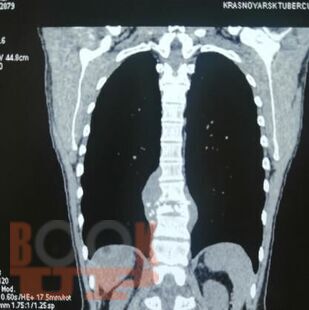

Учебное пособие составлено в соответствии с требованиями ФГОС ВО по специальностям 31.05.01 Лечебное дело и 31.05.02 Педиатрия, рабочей программы дисциплины «Фтизиатрия» (2018). В пособии собраны воедино и обобщены сведения о лучевой диагностике туберкулеза органов дыхания, включена клиническая классификация туберкулеза, иллюстрированная рентгенограммами больных, лечившихся в КГБУЗ «Красноярском краевом противотуберкулезном диспансере №1» с 1980-х г. по настоящее время.